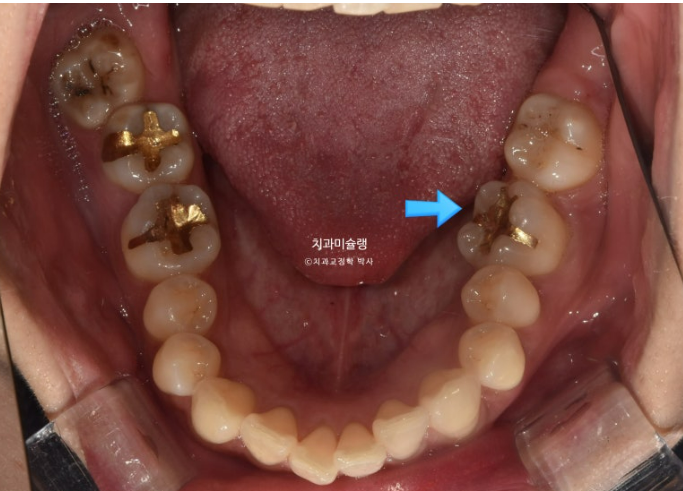

2년 전 교정치료를 위해 온 30대 환자분입니다. 파란 화살표 볼쪽으로 튀어나간 어금니들이 보입니다.

중심선 불일치도 보입니다.

좌측에는 가위교합이 소구치에 하나 대구치에 하나 총 2군데 있습니다.

교합을 담당하는 어금니 중 절반이 가위교합 상태이니, 좌측으로 씹기가 힘든 상태입니다.

아래 큰어금니는 안으로 쓰러져 있습니다.